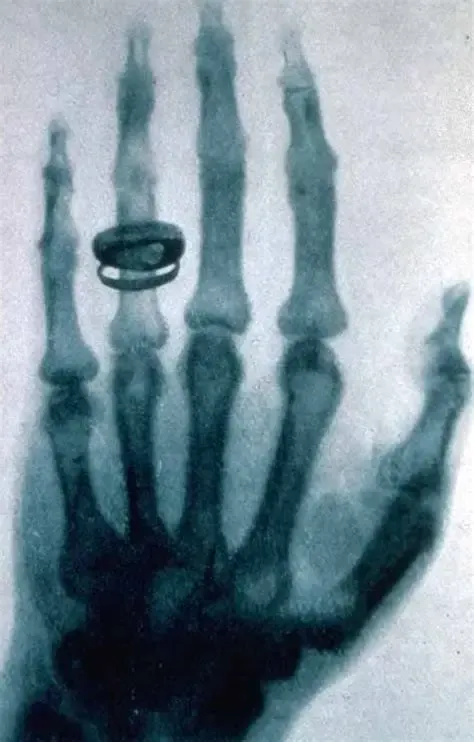

时间倒回1895年11月8日,德国维尔茨堡大学的物理实验室。那天晚上,伦琴像往常一样,在做阴极射线实验。他用黑纸把放电管严严实实地包起来,房间一片漆黑,他想看看射线能不能透出来。突然,他注意到一米开外,一个涂有荧光材料的小屏,居然闪了一下光。伦琴一愣:阴极射线不可能跑这么远啊!这黑纸包得死死的,光从哪来的?换成一般人,可能揉揉眼睛,以为是错觉,就下班回家了。但伦琴的“轴劲”上来了。他敏锐地意识到,这可能是一种全新的、未知的射线。接下来的六个星期,他吃住都在实验室,疯狂地实验。他用这种神秘的射线去照书本、照木板、照金属片……

发现X射线后,伦琴一夜之间成为世界名人。媒体疯狂报道,大众将他视为拥有“透视眼”的魔术师。商家也嗅到了金钱的味道。如果换作今天,伦琴马上可以申请核心专利,成立公司,市值千亿不是梦。事实上,当时确实有很多人找他谈合作,谈专利授权。但伦琴干了件让所有人目瞪口呆的事:他公开了所有研究成果,拒绝申请任何专利。他在报告里详细阐述了X射线的产生方法和特性,让全世界的科学家都能免费地继续研究。他说:“我的发现属于全人类。 我不希望它被任何利益所束缚,它应该以最可能快的方式为人类健康服务。”他甚至把获得的诺贝尔奖金,也全部捐给了自己的大学,用于支持科学研究。正因为他的无私,X射线技术以惊人的速度在全球普及。仅仅几个月后,美国医生就用它来为伤员寻找体内的子弹。不到一年,X光机就开始在医学诊断中扮演关键角色,拯救了无数生命。他放弃了成为巨富的机会,却让整个世界提前享受到了科学的福祉。这份胸襟,比诺贝尔奖牌更加闪亮。

无处不在的“X”今天,伦琴的发现早已融入我们生活的方方面面:去医院:骨折了、肺有问题、做肠胃检查,第一步就是“拍个片”。这“片”,就是X光片。它让医生拥有了“透视”的眼睛,是现代医学最基础的诊断工具之一。过安检:无论是机场、地铁还是重大活动,你的行李都要经过安检仪。那个屏幕上显示的物品轮廓,利用的就是X射线的穿透成像原理。工业探伤:大桥的钢结构、飞机的零部件、石油管道有没有内部裂缝?不用拆开,用X射线一照,缺陷一目了然。甚至去博物馆:鉴定古画真伪、查看青铜器内部结构,有时也会请出X射线这位“神探”。可以说,伦琴那一晚的荧光屏一闪,真正为我们点亮了一个“透明”的新世界。